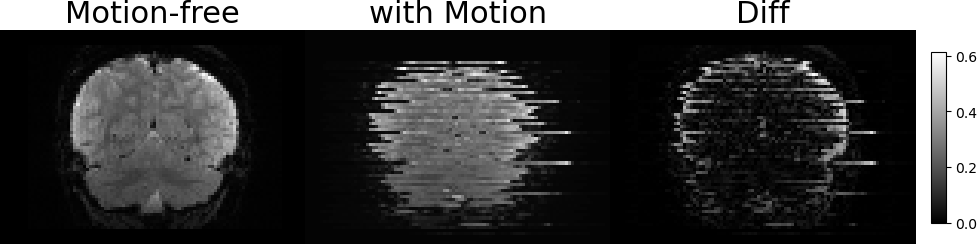

3.2 Representations of Transformations and Slices Generation

Figure 3: Illustration of the SVR problem. Two examples of free-motion volumes and volumes with synthetic motion. From left to right: Coronal LABEL:sub@fig1:a,LABEL:sub@fig1:b and Sagittal LABEL:sub@fig1:c,LABEL:sub@fig1:d views of the free-motion volumes, the generated volumes after applying the rigid transformations and sampling the slices, and the pixel-wise MSE between them, respectively. The artifacts due to the slice-level motion are visible in both Sagittal and Coronal views, however, they are not dipicted in the axial (imaging) axis of the image LABEL:sub@fig1:e,LABEL:sub@fig1:f.